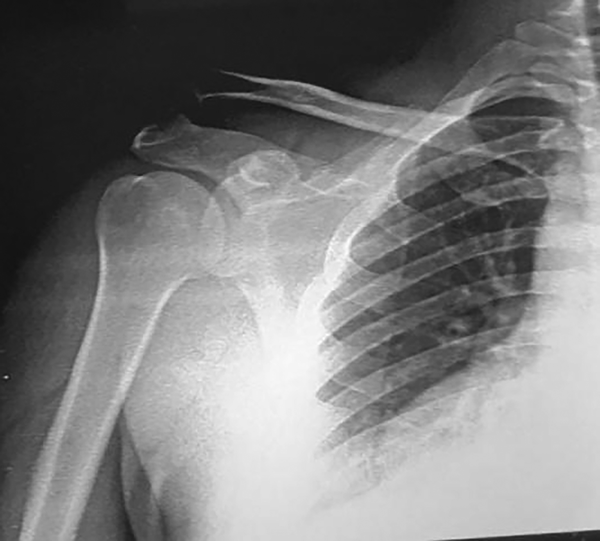

Paciente de sexo masculino, de treinta y nueve años, deportista, quien sufre caída desde su bicicleta, presenta dolor y limitación funcional para la abducción en hombro derecho. Al examen físico, dolor de fuerte intensidad a la digitopresión acompañado de aumento de volumen y deformidad en la articulación acromioclavicular, con signo de la tecla positivo (+) para luxación acromioclavicular. Se confirma el diagnóstico mediante estudio de imágenes basadas en Rx anteroposterior de hombro y proyección de Alexander, donde se clasificó, según Rockwood, en grado V (fig. 1).

Figura 1: Luxación acromioclavicular tipo V vista por Rx anteroposterior.